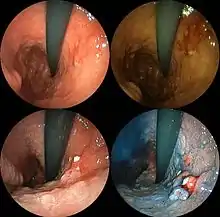

| A stomach ulcer that was diagnosed as cancer on biopsy and surgically removed | |

- Gastroscopic exam is the diagnostic method of choice. This involves insertion of a fibre optic camera into the stomach to visualise it.[35]

Abnormal tissue seen in a gastroscope examination is biopsied by the surgeon or gastroenterologist. This tissue is then sent to a pathologist for histological examination under a microscope to check for the presence of cancerous cells. A biopsy, with subsequent histological analysis, is the only sure way to confirm the presence of cancer cells.[35]

Various gastroscopic modalities have been developed to increase yield of detected mucosa with a dye that accentuates the cell structure and can identify areas of dysplasia. Endocytoscopy involves ultra-high magnification to visualise cellular structure to better determine areas of dysplasia. Other gastroscopic modalities such as optical coherence tomography are being tested investigationally for similar applications.[63]